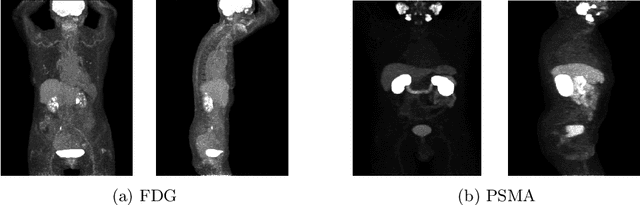

Abstract:Lesion segmentation in PET/CT imaging is essential for precise tumor characterization, which supports personalized treatment planning and enhances diagnostic precision in oncology. However, accurate manual segmentation of lesions is time-consuming and prone to inter-observer variability. Given the rising demand and clinical use of PET/CT, automated segmentation methods, particularly deep-learning-based approaches, have become increasingly more relevant. The autoPET III Challenge focuses on advancing automated segmentation of tumor lesions in PET/CT images in a multitracer multicenter setting, addressing the clinical need for quantitative, robust, and generalizable solutions. Building on previous challenges, the third iteration of the autoPET challenge introduces a more diverse dataset featuring two different tracers (FDG and PSMA) from two clinical centers. To this extent, we developed a classifier that identifies the tracer of the given PET/CT based on the Maximum Intensity Projection of the PET scan. We trained two individual nnUNet-ensembles for each tracer where anatomical labels are included as a multi-label task to enhance the model's performance. Our final submission achieves cross-validation Dice scores of 76.90% and 61.33% for the publicly available FDG and PSMA datasets, respectively. The code is available at https://github.com/hakal104/autoPETIII/ .